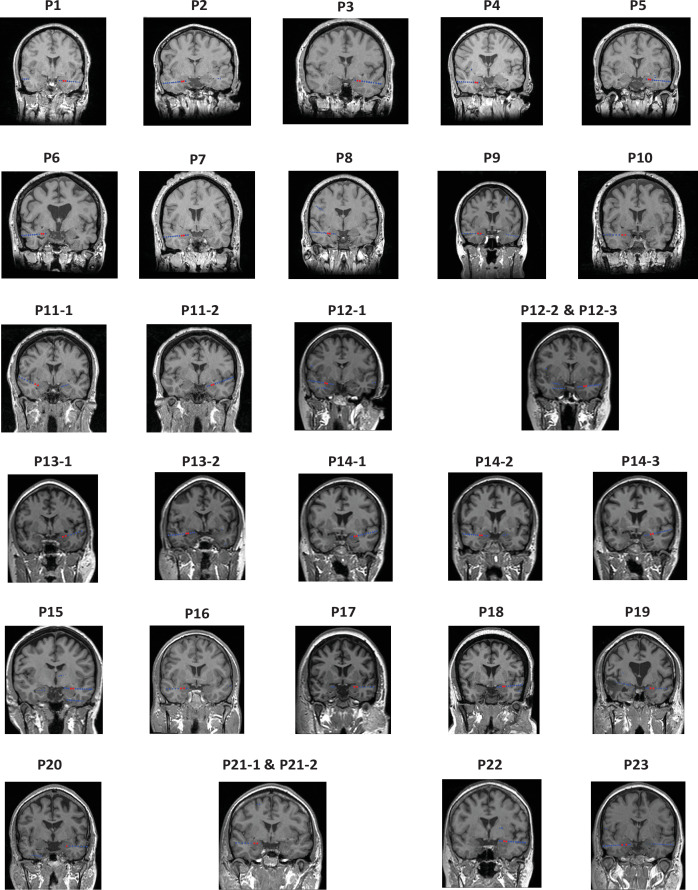

Direct electrical stimulation of the human brain has been used for numerous clinical and scientific applications. At present, however, little is known about how intracranial stimulation affects activity at the microscale. In this study, we recorded intracranial EEG data from a cohort of patients with medically refractory epilepsy as they completed a visual recognition memory task. During the memory task, brief trains of intracranial theta burst stimulation (TBS) were delivered to the basolateral amygdala (BLA). Using simultaneous microelectrode recordings, we isolated neurons in the hippocampus, amygdala, orbitofrontal cortex, and anterior cingulate cortex and tested whether stimulation enhanced or suppressed firing rates. Additionally, we characterized the properties of modulated neurons, clustered presumed excitatory and inhibitory neurons by waveform morphology, and examined the extent to which modulation affected memory task performance. We observed a subset of neurons (~30%) whose firing rate was modulated by TBS, exhibiting highly heterogeneous responses with respect to onset latency, duration, and direction of effect. Notably, location and baseline activity predicted which neurons were most susceptible to modulation, although the impact of this neuronal modulation on memory remains unclear. These findings advance our limited understanding of how focal electrical fields influence neuronal firing at the single-cell level.